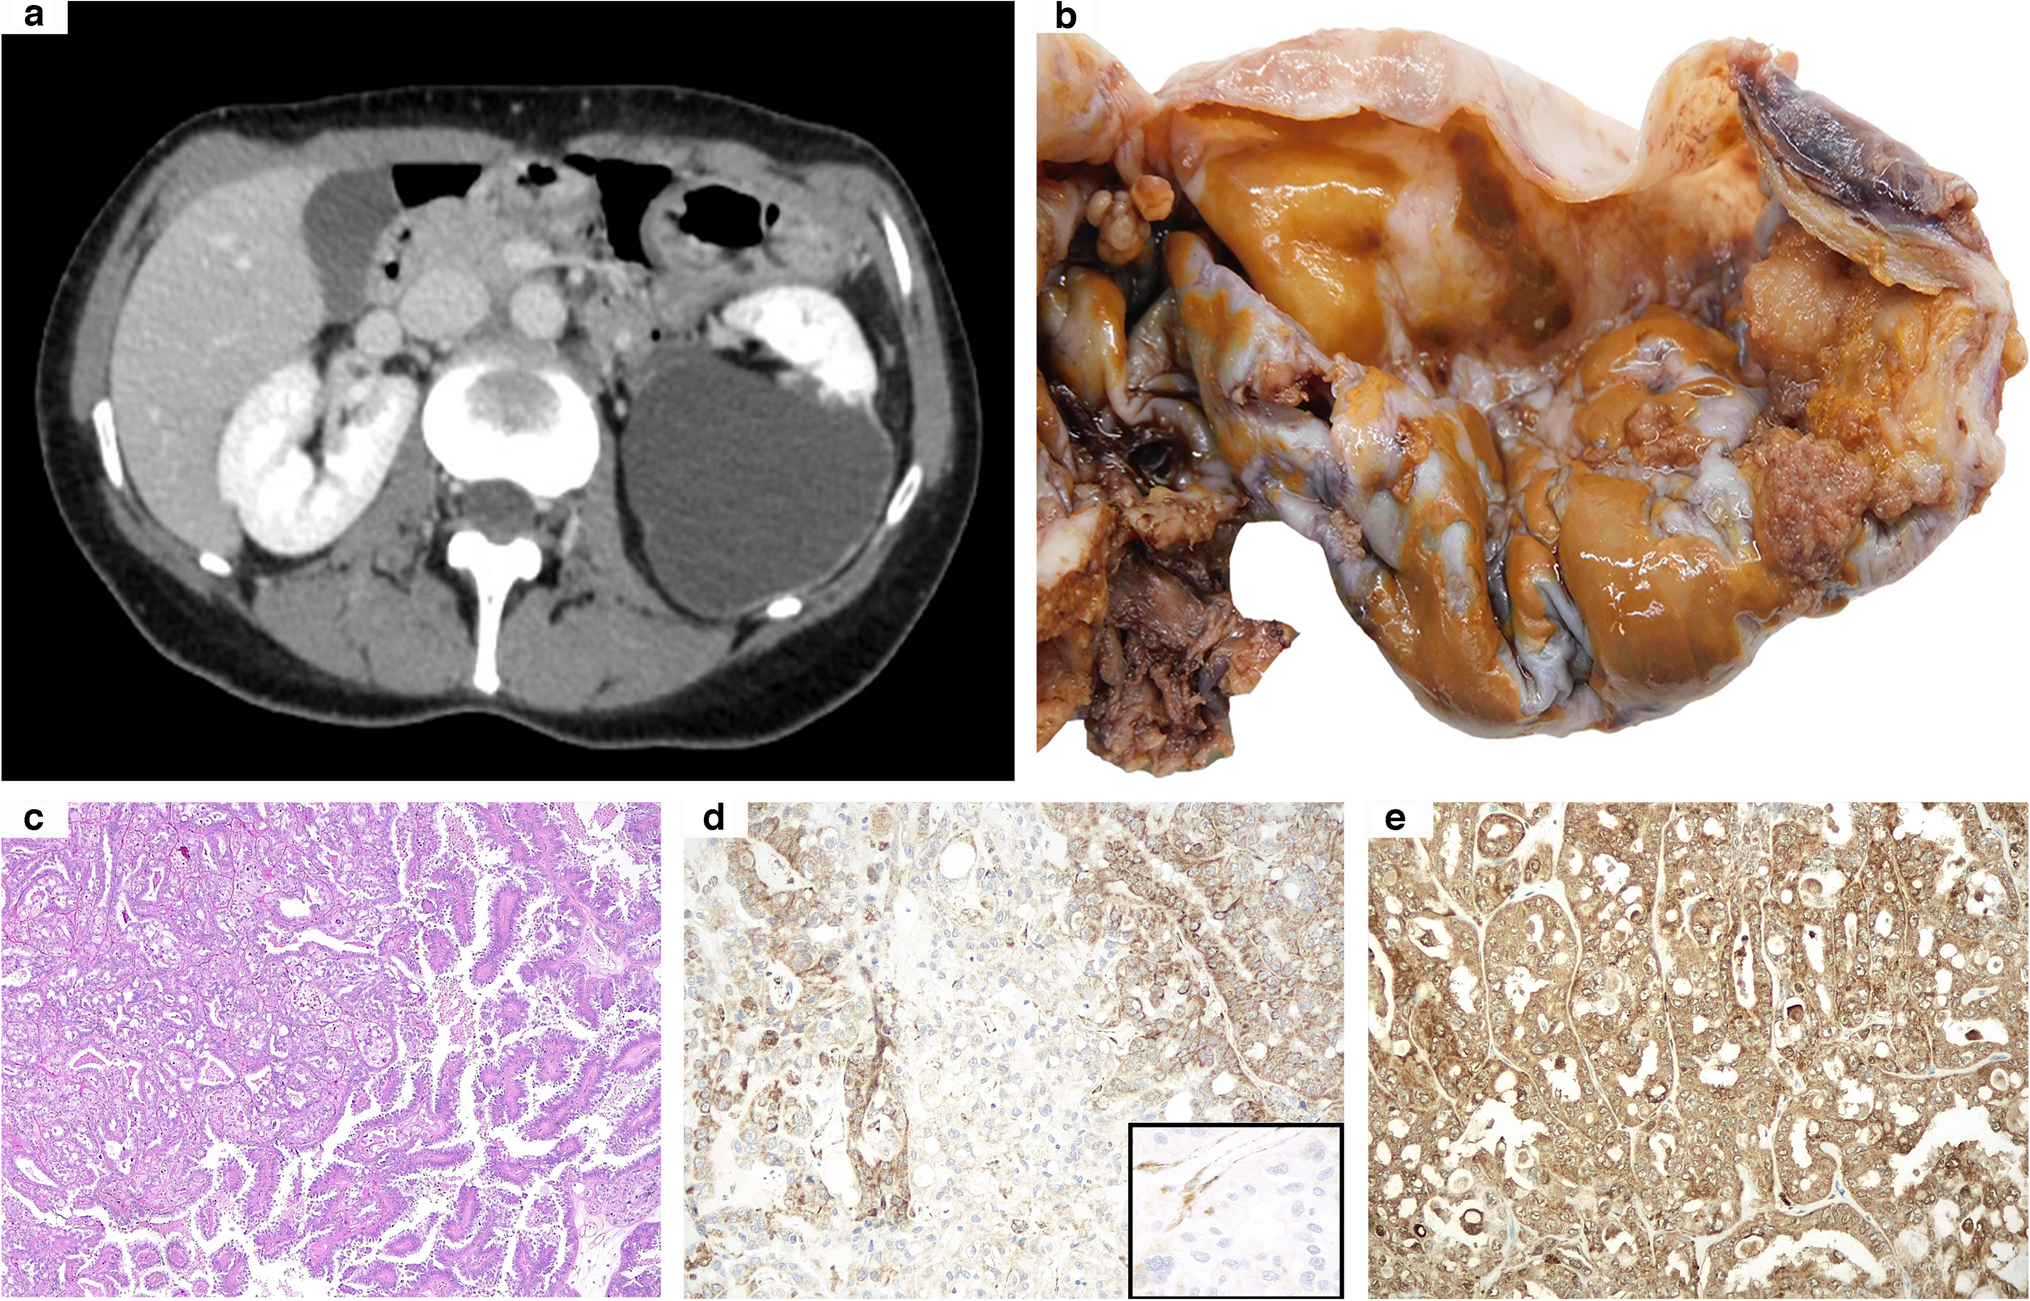

A 47-year-old woman, who had previously undergone hysterectomy for uterine leiomyomas, received partial nephrectomy for a single cystic mass of the left kidney, classified as Bosniak IV at preoperative radiological imaging (Fig. 1a). Grossly, the surgical specimen was composed of a 6.5-cm predominantly cystic lesion with several brownish papillary-like areas in the inner surface (Fig. 1b). At histological examination, a neoplastic proliferation arranged in various architectural growth patterns was observed (Fig. 1c), including papillary (80%), tubule-glandular (10%), solid (5%), and sieve-like (5%). Tumor cells showed abundant eosinophilic cytoplasm and roundish nuclei with prominent nucleoli (G3 sec. ISUP/WHO 2022). Coagulative tumoral necrosis was variably spotted. On follow-up, multiple peritoneal nodules were discovered, so that she was given a combined therapy based on an anti-angiogenetic drug (cabozantinib) and an immune-checkpoint inhibitor (nivolumab), still ongoing at the time of the present manuscript. Genetic tests were carried out based on the clinical and pathological findings, revealing a germline alteration of the FH gene (c.698G > A). Moreover, an identical mutation of the same gene was also identified in one of the patient’s sons, further confirming the underlying hereditary syndrome.

Fig. 1

Abdominal CT scan from case 10 revealing a 7-cm predominantly cystic left renal mass (a). At gross examination, the inner cystic wall was partially filled with brownish papillary-looking protrusions (b). Morphologically, papillary and tubule-glandular architectural growth patterns were closely admixed (c). Immunohistochemical analysis showed a patchy FH loss: while some tumor areas partially retained its expression, others revealed clear-cut negativity with positive endothelial cells serving as internal control (d and inset). However, strong and diffuse 2SC staining supported the diagnosis of FH-deficient renal cell carcinoma (e) (original magnifications 50X (c), 200X (d, e), and 400X inset)

All but one kidney tumor and metastatic localizations revealed diffuse FH immunohistochemical loss, apart from the primary renal neoplasm from case 10, which displayed a faint retained expression of such a marker in about 20% of the cells (Fig. 1d and inset). Moreover, in case 9, despite the fact that some areas could be confidently labeled as FH-negative, in others, the immune infiltrate’s marked effacement of the neoplastic cells made identifying FH loss a challenging task (Fig. 4e, f). Similarly, diffuse and intense cytoplasmic and nuclear 2SC staining was observed in all primary and secondary samples in the wide majority of neoplastic cells, ranging from 50 to 100%, including the doubtful cases 9 and 10 and the small biopsy from case 11 (Figs. 1e, 2d, and 4g).